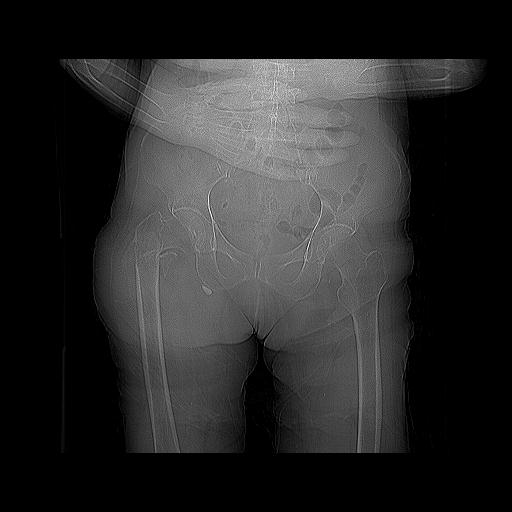

100703 1/27 両股正面+軸 1/29 両股正面+軸 94歳女性 パンソンロン